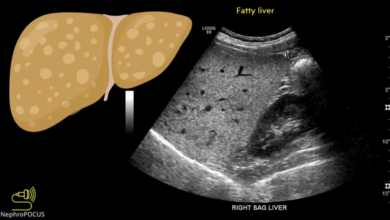

Liver Parenchyma: Understanding the Vital Organ

It performs a wide range of functions that are essential for our body’s metabolism, detoxification, and immune system. One of…

Understanding Heterogeneous Echotexture: Causes, Diagnosis, and Treatment Options

In the field of medical imaging, understanding the various textures and patterns observed in ultrasound scans is crucial for accurate…